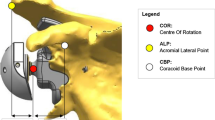

Reverse Baseplate Fixation

Since the initial use of the reverse total shoulder, the glenoid component fixation has been a common reason for early implant failure. The first generation of reverse total shoulder designs used a lateralized center of rotation for the glenoid side of the implant. Modifications of the design that medialized the center of rotation of the implant decreased the stresses of the glenoid baseplate and resulted in less loosening and less early failure [9]. New designs that allow for larger screws, locking screws, and variable screw angle insertion have improved the initial fixation of the glenoid baseplate as well. As the implant fixation methods have improved, implant designers have changed the center of rotation of the reverse constructs to more lateralized designs to help minimize the complications that occur with medialization. Some authors have described less scapular notching when the center of rotation is lateralized because the medial calcar of the humeral implant is less likely to impinge on the scapula [5, 59, 82, 88]. Other biomechanical considerations have improved the surgical technique used to insert the baseplate, and these have been tested in biomechanical studies. Some modifications that are more difficult to test in the lab include bone ingrowth technology. These biologic solutions cannot be simulated with our current biomechanical experiments, so we must rely on long-term clinical follow-up before knowing how well these factors affect the stability of the glenoid baseplates.

Some of the earlier biomechanical studies focused on the effect of the screws used to fix the glenoid baseplate. Chebli et al. used a sawbone model to fix a glenoid baseplate with multiple variations in screw configurations [16]. The authors found that the inferior screw was the most important because fixation strength was 35 % weaker when that screw was omitted. The strength of the fixation was 16 % weaker if the superior screw was omitted. Harmen et al. compared the fixation of the Encore reverse baseplate fixation, which uses 4 locking screws and a central non-locking screw with a flat baseplate to the Depuy Delta III baseplate fixation, which uses two locking screws and two non-locking screws to fix a flat baseplate with a central peg [39]. The Encore design used a lateralized center of rotation which exerts a 69 % higher load onto the baseplate compared to the Delta III design that has a more medialized center of rotation. The micromotion of both designs was below the threshold of 150 μ that is required to obtain bone ingrowth into the implants. If the Encore baseplate was fixed with non-locking screws, the micromotion was above the 150 μ threshold.

The number of screws used to fix the glenoid has also become a question for debate as different designs use multiple screw configurations. All designs incorporate at a minimum a superior and inferior screw, which are commonly locked to the plate. Many designs also include a screw that can be fixed in the center of the glenoid baseplate that engages the cortical bone in the middle column of the scapula. Other designs allow for an anterior and posterior screw to be placed, but the bone can be thin and soft in these positions after the glenoid has been reamed, especially in smaller women. When the posterior screw engages both the glenoid cortex and the cortex of the scapular spine, the stability of the glenoid implant has been shown to improve significantly by two separate studies [23, 45]. The problem with using this type of configuration is that the screw can potentially injure the suprascapular nerve as it courses around the base of the scapular spine [40, 68, 98]. James et al. studied the effect of using two locking screws alone compared to two locking screws in addition to two non-locking screws in the anterior and posterior positions. They did not find any difference between the micromotion of the glenoid baseplate in their cadaver model [52].

It is often difficult to apply the results of one biomechanical study that uses a specific implant to another implant that may have other important design characteristics that influence initial fixation of the implant. These design differences include backside geometry such as flat-backed or curve-backed designs. Curved-backed designs have been showed to improve initial stability in biomechanical testing, but they have the disadvantage of removing more cortical bone on the inferior glenoid due to the more inferior positioning of the implant compared to an anatomic implant [52]. This inferior placement is done to avoid notching of the scapula by the medial calcar of the humeral implant. The inclination of the glenoid implant also plays a critical role in the initial fixation of the implant and the likelihood of causing of scapular notching. Some authors have shown that inferior tilt of the glenosphere improves the mechanics of the implant and decreases the micromotion in sawbone models [38]. In an effort to minimize notching that was often seen with medialized glenoid designs, the glenosphere was changed to allow for inferior eccentric placement of the glenosphere on the baseplate. This allows the humeral component to be pushed more inferior and allows for more clearance before the humerus could impinge on the scapula. The biomechanical effect of this design compared to the medialized concentric design and a lateralized design was studied by Gutierrez et al. They found better mechanics and less rocking horse potential when the concentric and lateralized design was placed with inferior tilt, but the eccentric design had the best biomechanical stability when it was placed without any tilt [37] (Fig. 6.19).

This is an illustration of the effect of different forces at the baseplate-bone interface. Each glenosphere configuration (concentric, lateral eccentric, and inferior eccentric) can be placed in differing tilts to produce more even forces at the baseplate-bone interface. These forces are optimum for concentric and lateral eccentric glenospheres when placed in inferior tilt, while for inferior eccentric glenospheres, the optimal tilt is neutral; this placement will cause the least amount of rocking. The other tilts lead to more uneven forces at the baseplate-bone junction and hence, increased rocking (Reprinted from Gutierrez et al. [38] with permission from Elsevier)